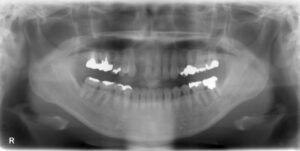

下顎臼歯4本欠損症例

BEFORE AFTER 52歳女性/下4本欠損/インプラント埋込手術 【治療内容】 左下第二小臼歯、第一大臼歯、第二大…